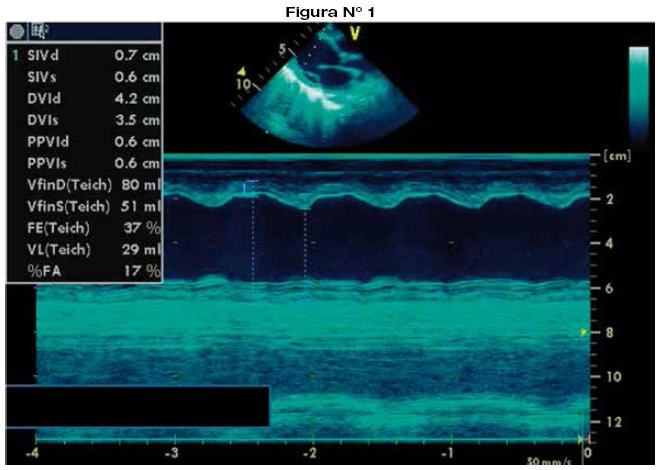

La evaluación de la función ventricular debe individualizarse en cada paciente, ya que debe tenerse en cuenta que varios factores, principalmente la presencia de cardiopatía congénita, pueden modificar la geometría ventricular dificultando la interpretación real de la fracción de eyección ya sea del ventrículo izquierdo, del ventrículo derecho o del univentriculo7-9,22,23. El ecocardiograma es la herramienta incruenta más útil para evaluar la función del ventrículo izquierdo tanto en proyección apical de cuatro cámaras como en el eje paraesternal largo (aplicando modo-M), solo con algunas limitaciones relacionadas con la alteración de la geometría de dicho ventrículo como la edad menor de 5 días (septo interventricular rectificado por patrón fetal residual), movimiento paradójico del septo interventricular, perdida de la movilidad parietal o septal. Sin embargo existen otros parámetros ecocardiograficos que permiten la evaluación como el índice de Tei izquierdo o la excursión del anillo mitral (MAPSE)22. La evaluación dirigida de la función sistólica del ventrículo derecho aún es un desafío por su compleja morfología24. Por ello, es importante la evaluación del ventrículo derecho desde varias proyecciones25-27. Se evalúan la fracción de acortamiento del área del ventrículo derecho28, la excursión sistólica del anillo tricuspídeo (TAPSE)29, el Doppler pulsado tisular del anillo tricuspídeo e índice de performance miocárdico (índice de Tei)29,30.